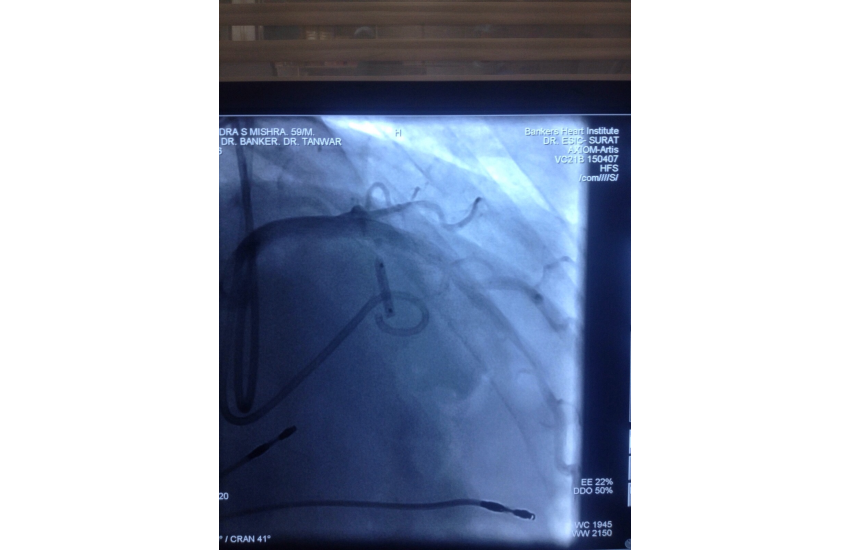

CAG revealed normal coronaries,holter shows sinus bradycardia,RBBB with LAHB,intermittent AF, TMT shows blunted chronotropic response and hypotensive response so he has been planned for PPI with back up of pacemaker patient treated with beta blockers and corderone,after 7 days of PPI,he has undergone alcohol septal ablation successfully,prior his dynaemic gradient was 50 mmhg in rest n 80 mmhg with exercise which reduced to 20mmhg after procedure. Now patient is under close follow up so will continue updating.